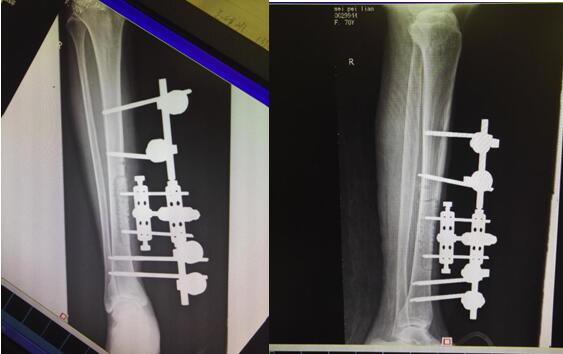

注:术后影像学检查。